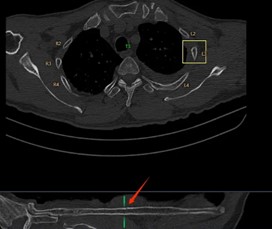

在一些大型醫(yī)院和醫(yī)療研究機構,已經開始嘗試這種協(xié)作模式。例如,在胸部CT肺結節(jié)以及肋骨骨折的影像診斷中,AI 首先對影像進行分析,標記出可能的異常區(qū)域,醫(yī)生再對這些區(qū)域進行詳細觀察和診斷。通過這種協(xié)作,不僅提高了診斷效率,還提升了診斷的準確性。